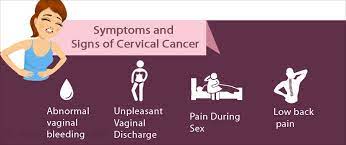

Cervical cancer: What are the signs and symptoms?

January marks Cervical Cancer Awareness Month. Cervical cancer – which develops in a woman’s cervix – is the fourth-most common cancer in women, according to the World Health Organization (WHO). The agency reports that more than 300,000 women die from cervical cancer every year and that an estimated 570 000 women were diagnosed with cervical cancer around the world in…